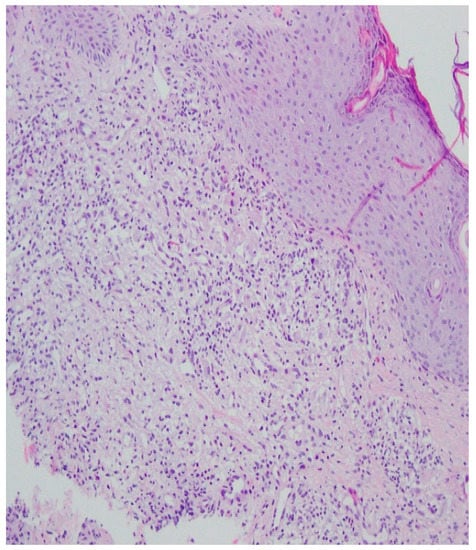

A histopathological examination of the skin lesion performed during hospitalisation revealed a thickened non-regular epidermis with streaky swelling, thinned by lymphocytic and histiocytic inflammatory infiltration with single plasmacytes. Slightly thicker infiltration presented in the area of enlarged vessels of the superficial plexus. There was a lack of characteristics typical for active pyoderma gangrenosum. This clinical picture can be consistent with secondary/tertiary syphilis (Figure 8 and Figure 9).

Figure 8.

Thickened non-regular epidermis with streaky swelling, thinned by lymphocytic and histiocytic inflammatory infiltration with single plasmacytes. Slightly thicker infiltration in the area of enlarged vessels of the superficial plexus. Lack of characteristics typical for active pyoderma gangrenosum. The clinical picture can be consistent with secondary/tertiary syphilis.

A revision of the biopsy from September 2021 showed a thickened epidermis and lymphocytic and histiocytic inflammatory infiltration with multiple plasmacytes (Figure 10 and Figure 11).

Figure 10.

Thickened epidermis. Lymphocytic and histiocytic inflammatory infiltration with multiple plasmacytes. Histopathological picture and data from the history are consistent with syphilis.

The histological picture in late syphilis is characterised by a proliferative reaction with a tendency for necrosis and perivascular infiltrations of lymphocytes, histiocytes and plasma cells [83].